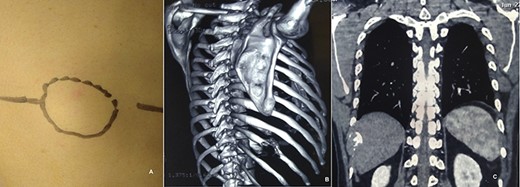

A 15-year-old girl present with lump in right chest with gradually progressing discomfort of 6-month duration. The discomfort was constant with intermittent exacerbation. She had no history of trauma or prior chest surgery, and her past medical history was unremarkable. Her physical examination revealed a palpable mildly tender mass on sixth rib on anterolateral wall of the right chest. Her routine laboratory test results, including complete blood count, erythrocyte sedimentation rate, renal function test and liver function tests, were all within normal range. Chest radiograph performed showed destruction of right sixth rib (Fig. 1A). CT chest revealed 36 × 30 × 80 mm well-defined large uniloculated cystic lesion of the sixth rib involving anterolateral part and abutting the costochondral junction (Figs 1B and C). She underwent surgery after all diagnostic investigation was completed.

CXR (A, arrow) showing mass lesion in sixth rib. CT chest axial (B, arrow) and saggital (C) showing uniloculated bone cyst.